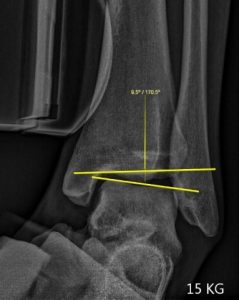

Le Telos Stress est un appareil permettant de réaliser les examens en salle de radiologie visant à tester la stabilité et quantifier la laxité des ligaments des  articulations.

Cet Appareil est particulièrement adapté à l’étude fonctionnelle des ligaments croisés des genoux LCA et LCP et ligaments collatéraux des chevilles avant toutes décisions thérapeutique ou chirurgicale.

La méthode est précise et reproductible car le positionnement est toujours identique et la force exercée est étalonnée.

Les mesures réalisées sur les images radiographiques permettent d’obtenir un diagnostic précis pour le prescripteur.